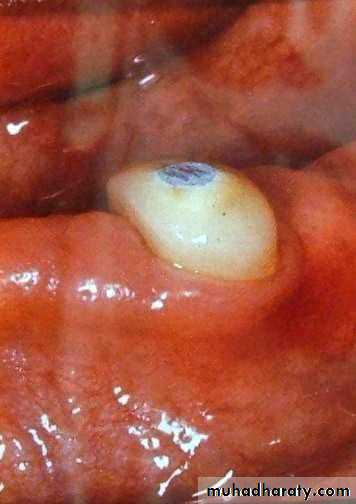

• 4) Short (1-2mm):

• a) conform to the curvature of the alveolar ridge (Dum-shape).• b) very low profile.

• c) indicated for max. favourable C/R

• ratio.

• d) can be used with the stud

• attachment.

• May be with or without amalgam plug.

• 5) Submerged root:

• Abutment reduced to level below gingival margin, so need extra retentive attachment (intracoronally).• RCF .... if needed